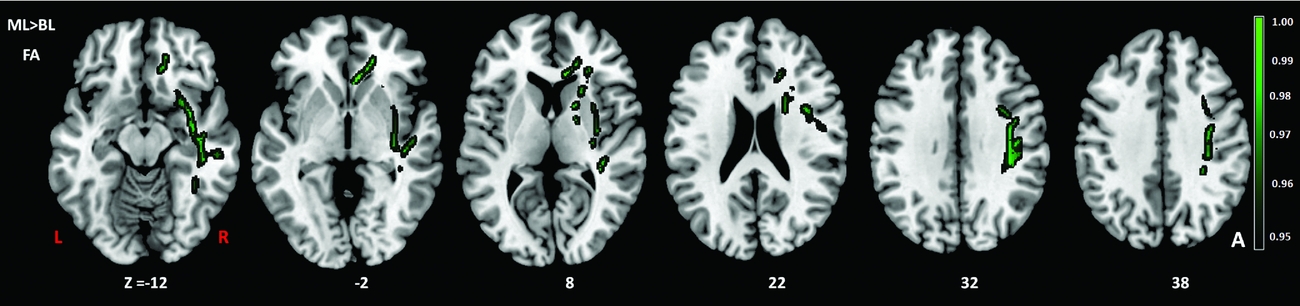

Comparison of the DTI measures between monolingual and bilingual speakers (Monolingual > Bilingual) found reduced mean FA (p<.05) in the right anterior thalamic radiation, ILF and IFOF (Figure 1). Reverse contrasts between bilingual and monolingual speakers (Bilingual > Monolingual) were not significant. TBSS revealed higher mean MD for bilinguals in forceps minor and bilateral SLF (Figure 2, Panel A). Bilinguals also had higher mean RD in forceps minor, right SLF, ILF and the right anterior thalamic radiation (Figure 2, Panel B) and higher mean AD in forceps minor, right SLF and right anterior thalamic radiation (Figure 2, Panel C). Comparisons between monolingual and bilingual speakers (Monolingual > Bilingual) found no significant differences in mean MD, RD or AD (p>0.05). For bilingual speakers, there was a positive correlation (r=0.424) between average L2 proficiency score and mean RD in the right SLF (p<0.07) (see Figures 4 and 5, for details). A summary of the TBSS analyses of regions where mean RD correlated with average L2 proficiency for bilinguals is shown in Figure 4 and Figure 5 shows the plot of mean RD and average L2 proficiency in the right SLF. A component L2 proficiency index was constructed comprising speaking, reading, writing and comprehension scores and it revealed significant correlations between speaking in L2 (p<0.07) and writing in L2 (p<0.05) with mean RD values in right SLF (see Table 5).

Figure 2. TBSS results showing group differences in fractional anisotropy (FA) (green) expressed in 1-P values (p=0.05, corrected) and overlaid onto MNI152 template. TIV (total intracranial volume) was added as a regressor in the analysis to ensure that differences in TIV between the groups did not contribute to other variables. BL=Bilinguals, ML=Monolinguals.

The results support our expectations that white matter microscopic differences will be found in white matter tracts for bilingual compared to monolingual speakers. We observed higher mean MD, RD and AD for bilingual speakers in forceps minor and right SLF and a positive correlation between L2 proficiency and mean RD in the right SLF. Furthermore, as reported by Cummine and Boliek (Reference Cummine and Boliek2013) with a comparable sample, we confirmed reduced mean FA for bilinguals in the anterior thalamic radiation and the right IFOF. However, unlike Cummine and Boliek (Reference Cummine and Boliek2013) we did not find reduced MD in forceps minor or left IFOF or no evidence of increased MD in the cingulum for bilingual speakers. Other studies using different samples also report differences in mean FA, MD and RD between monolingual and bilingual speakers (Gold et al., Reference Gold, Johnson and Powell2013; Luk et al., Reference Luk, Bialystok, Craik and Grady2011; Kuhl, Richards, Stevenson, Can, Wroblewski, Fish & Mizrahi, Reference Kuhl, Richards, Stevenson, Can, Wroblewski, Fish and Mizrahi2013; Plitsiakis et al., Reference Pliatsikas, Moschopoulou and Saddy2015). However, we show for the first time that mean axial diffusivity (AD) is greater for bilingual than monolingual speakers in forceps minor and right SLF. We note that the same pattern was observed in the right SLF for mean MD and RD and moreover that the right SLF is implicated in neuroplasticity after second language experience (cfr. Qi et al., Reference Qi, Han, Garel, San and Gabrieli2015 discussed below). We discuss the implications of these results for models of bilingual language processing in detail below.

Bilingual adults had higher mean MD values in bilateral SLF and forceps minor, higher mean RD in right SLF, forceps minor and higher mean AD in right SLF and forceps minor. These findings converge on a pattern that reflects the role of language control in bilingual speech in our view. It is of interest that higher mean RD and mean AD in the anterior thalamic radiation are coincident with lower FA in the same region which may indicate a different pattern of myelination. Furthermore, mean FA is in fact lower for bilingual speakers than monolingual speakers. One possible inference is that higher RD and AD, which characterize the rate of diffusion in the perpendicular and parallel directions respectively, indicate a higher rate of isotropic diffusivity in bilinguals but lower axonal density, myelination and coherence in the orientation of white matter as reflected in mean FA. However, although myelination may be reflected in changes to mean axial and radial diffusivities, the underlying mechanisms are complex. Myelination is not a necessary condition for anisotropy and an increase reflects coherent organization of the fibre tracts within the voxel more than myelination per se. Other factors such as the variability in axonal dimensions, membrane permeability, membrane packing density and extra cellular spacing between axons may contribute to mean FA values. Indeed, results from computer simulations suggest axonal diameter and membrane permeability affect transverse (or perpendicular) ADC (Beaulieu, Reference Beaulieu2002). Moreover, unlike

The strongest evidence for our contention that DTI metrics index enlarged and less prolate myelination in white microstructure due to bilingual experience with a second language is the correlation between average L2 proficiency and mean RD in the right SLF (Figures 4 and 5) and the correlations between mean writing and speaking sub-scores and mean RD values in the right SLF (Table 5). Given the established role of SLF pathways in language production (Dick & Tremblay, Reference Dick and Tremblay2012; Kamali, Flanders, Brody, Hunter & Khader, Reference Kamali, Flanders, Brody, Hunter and Khader2014; Thiebaut de Schotten, Acqua, Forkel, Simmons, Vergani, Murphy & Catani, Reference Thiebaut de Schotten, Acqua, Forkel, Simmons, Vergani, Murphy and Catani2011), we contend that the reliable white matter microstructural changes observed in the right SLF can be attributed to speaking more than one language at a minimum. The novelty of our findings concerns AD and RD. We know that FA and MD reflect neuroplasticity in the language system including second language learning. The effects of second language immersion on FA was reported in a longitudinal study by Schlegel et al. (Reference Schlegel, Rudelson and Tse2012) who found that nine month immersion in L2 (Mandarin) was correlated with increased mean FA in the genu of the CC for native English speakers. Changes in mean FA are also correlated with language training-induced increases in the strength of the structural connectivity between the inferior frontal gyrus and caudate in the right hemisphere. For example, Hosoda et al. (Reference Hosoda, Tanaka, Nariai, Honda and Hanakawa2013) reported that Japanese (L1) learners of English (L2) had an increase in mean FA in the right ILF after training and showed that L2 proficiency was correlated with mean FA in the right ILF. Although we observed a relationship between mean FA and second language experience in the right ILF, the effect was in the opposite direction to Hosoda et al., i.e., it is reduced for bilingual speakers. Moreover we found RD was greater in the ILF for bilingual speakers showing that FA and RD are dissociable processes that follow bilingual language experience in our sample. On the latter point, we stress that bilingual language experience in our study is a binary, fixed variable whereas second language exposure is a continuous, random variable in the study by Hosoda et al. (Reference Hosoda, Tanaka, Nariai, Honda and Hanakawa2013). Therefore, we are reluctant to make direct comparisons between studies. It is of interest however that the right ILF is sensitive to speaking more than one language. In a study of native English speakers who were also learning Mandarin, Qi et al. (Reference Qi, Han, Garel, San and Gabrieli2015) report that average RD was correlated with language proficiency following second language training and with increased mean FA in the right ILF and also in the right SLF. Our finding of increased RD in right SLF is compatible with their results and suggests effects of neuroplasticity reflect bilingual language experience that is not specific to the language or the type of language experience. We therefore disagree with one of the conclusions of Qi et al. who argue their results reflected language specific properties e.g., the use of pitch contour (tone) and visuospatial skills for learning Mandarin. Our results show effects in right SLF for native Hindi speakers who use English regularly and there are no similarities between Hindi and Mandarin. In our view it is remarkable that the right ILF is a sensitive measure of second language experience across different language types. Comparing results to Qi et al. (Reference Qi, Han, Garel, San and Gabrieli2015), we contend a broader role for the SLF in second language exposure that is not limited to the training effects that inevitably result from learning a second language. However, we agree with the conclusions of Qi et al. (Reference Qi, Han, Garel, San and Gabrieli2015) that differences in linguistic attributes between first and second languages may underpin correlations between mean RD and speaking and writing attainment in a second language (see Table 5). Since our sample was early immersed in L2 (compared to the late learners in a training study), changes due to training might have been in evidence at an earlier age for our sample but have stabilized over time. As Qi et al. argue, right hemisphere involvement in second language learning is most likely not a unique feature of the linguistic properties of a second language and is likely due to the recruitment of brain regions outside the native language network that reflect the cognitive demands that arise from second language use. This hypothesis gains support from significant associations observed between mean RD in right SLF and ILF for bilinguals here. Our results add to those from Qi et al. (Reference Qi, Han, Garel, San and Gabrieli2015) in terms of the mean AD and RD measures. Qi et al. (Reference Qi, Han, Garel, San and Gabrieli2015) reported a negative correlation between mean RD and no correlation between mean AD and second language proficiency whereas we found mean AD and RD are both higher in bilingual speakers and mean RD is correlated with proficiency in a second language (English). Hence, results from lifelong Hindi–English bilingual speaking students are different from the findings from native English speaking students who learn a new language (Mandarin) over a much shorter period of time. Comparisons between these studies suggest that (functionally) reports of white matter microscopic changes after second language experience or exposure should distinguish between samples whereby the second language is early acquired and then used routinely in a multilingual environment (Delhi) compared to late acquired learning of a second language in a constrained environment such as the classroom.

Cummine and Boliek (Reference Cummine and Boliek2013) report reduced MD for bilingual young adults in forceps minor (and left IFOF) together with increased MD in the cingulum. Sagi, Tavor, Hofstetter, Tzur-Moryosef, Blumenfeld-Katzir & Assaf (Reference Sagi, Tavor, Hofstetter, Tzur-Moryosef, Blumenfeld-Katzir and Assaf2012) proposed that MD measures astrocyte swelling and remodeling of glial processes reflecting neuroplasticity (see also Alexander, Lee, Lazar & Field, Reference Alexander, Lee, Lazar and Field2007; Song, Yoshino, Le, Lin, Sun, Cross & Armstrong, Reference Song, Yoshino, Le, Lin, Sun, Cross and Armstrong2005). Therefore, it is unremarkable that MD is higher for bilinguals but puzzling that Cummine and Boliek (Reference Cummine and Boliek2013) report the opposite effect. Of deeper interest is the lateralization of AD and RD effects to the right hemisphere for our sample. RD is related to myelination. TBSS analysis and histogram measures (Table 4) show a consistent pattern of differences in mean AD, RD and MD effects in SLF but the AD and RD indices are observed in right SLF only. According to Qi et al. (Reference Qi, Han, Garel, San and Gabrieli2015) lower RD reflects axonal myelination or denser axonal tracts whereas AD measures axon integrity. Whereas Qi et al. (Reference Qi, Han, Garel, San and Gabrieli2015) found an inverse correlation between FA and RD (but not AD) with higher FA values associated with lower RD for second language learners, we found the reverse pattern (lower FA and higher RD) for bilingual speakers. Qi et al. (Reference Qi, Han, Garel, San and Gabrieli2015) proposed second language learning increases myelination leading to denser axonal tracts in SLF. However, we cannot reconcile this account with our data unless we assume that bilingual experience is different to second language learning. We noticed Qi et al. (Reference Qi, Han, Garel, San and Gabrieli2015) reported average values across SLF regions in their analyses. However, the SLF is divided into at least four parts including the arcuate and temporo-parietal SLF (Thiebaut de Schotten et al., Reference Thiebaut de Schotten, Acqua, Forkel, Simmons, Vergani, Murphy and Catani2011). When overlays are applied to SLF regions (following the method reported by Kamali et al., Reference Kamali, Flanders, Brody, Hunter and Khader2014), we found that mean MD was associated more with SLF III. SLF III originates in the supramarginal gyrus and terminates in ventral premotor and prefrontal cortex – a region that is associated with practice on cognitive tasks (Wang & Weekes, Reference Wang and Weekes2014). Schmahmann and Pandya (Reference Schmahmann and Pandya2006) propose that somatosensory information related to language articulation is conveyed via SLF III. As outlined above, if we compare our data to comparable effects from language learning we see correlated but dissociable patterns of myelination. In our view it is lifelong bilingual language experience that generates neuroplasticity and this is reflected in greater isotropic diffusivity. Given that increases in MD observed here are accompanied by increases in AD and RD (as expected), we assert that bilingual language experience is a valid measure of neuroplasticity when compared to training studies and moreover it is cumulative exposure not learning per se that leads to less prolate and spherical (increased axon) diameter.

We found little evidence that left hemisphere networks and tracts become more important as language proficiency improves at least when the language is early acquired and used daily. It is also notable that studies with simultaneous interpreters compared to matched monolingual controls report decreases in FA at the whole brain level that accompany increases in RD and decreases in AD in the CC, the cortico-spinal tract and cingulum bundle (Elmer, Hanggi, Meyer & Jancke, Reference Elmer, Hanggi, Meyer and Jancke2011). Differences were attributed to demands in sensory-motor coupling mechanisms necessary for simultaneous interpreters in regions supporting articulation such as forceps minor (Figure 1).